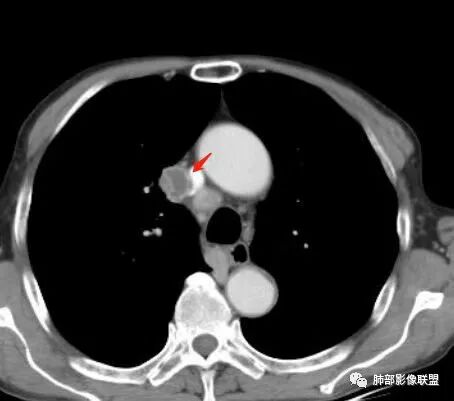

这次,半月,左胸痛不适,高热:39°C,白细胞、中性粒细胞高

主病灶在右上叶尖段、前段纵隔旁,紧贴胸膜

楔形、边缘膨隆,附近见斑片状、网格状高密度影

支气管近端堵塞,可惜显示的不一定全面

支气管壁还是弥漫增厚

中央坏死明确

整体内壁偏清楚,似乎有些地方欠清,不知道是否厚层所致

整体而言:远侧、内侧壁厚

坏死明显,这类膨隆就不支持生长速度不一致所致,而支持坏死朝周围的压力导致边缘的膨隆

这里倒是符合血管的压迫

与胸膜的关系?分界还算清楚

最让人忐忑的:淋巴结

炎性:结核多见,肿瘤:鳞癌多见

最让人放心不下的是这里

南边  :

上腔静脉外面按理没有淋巴结啊

其次:团块影的壁:厚薄不均匀